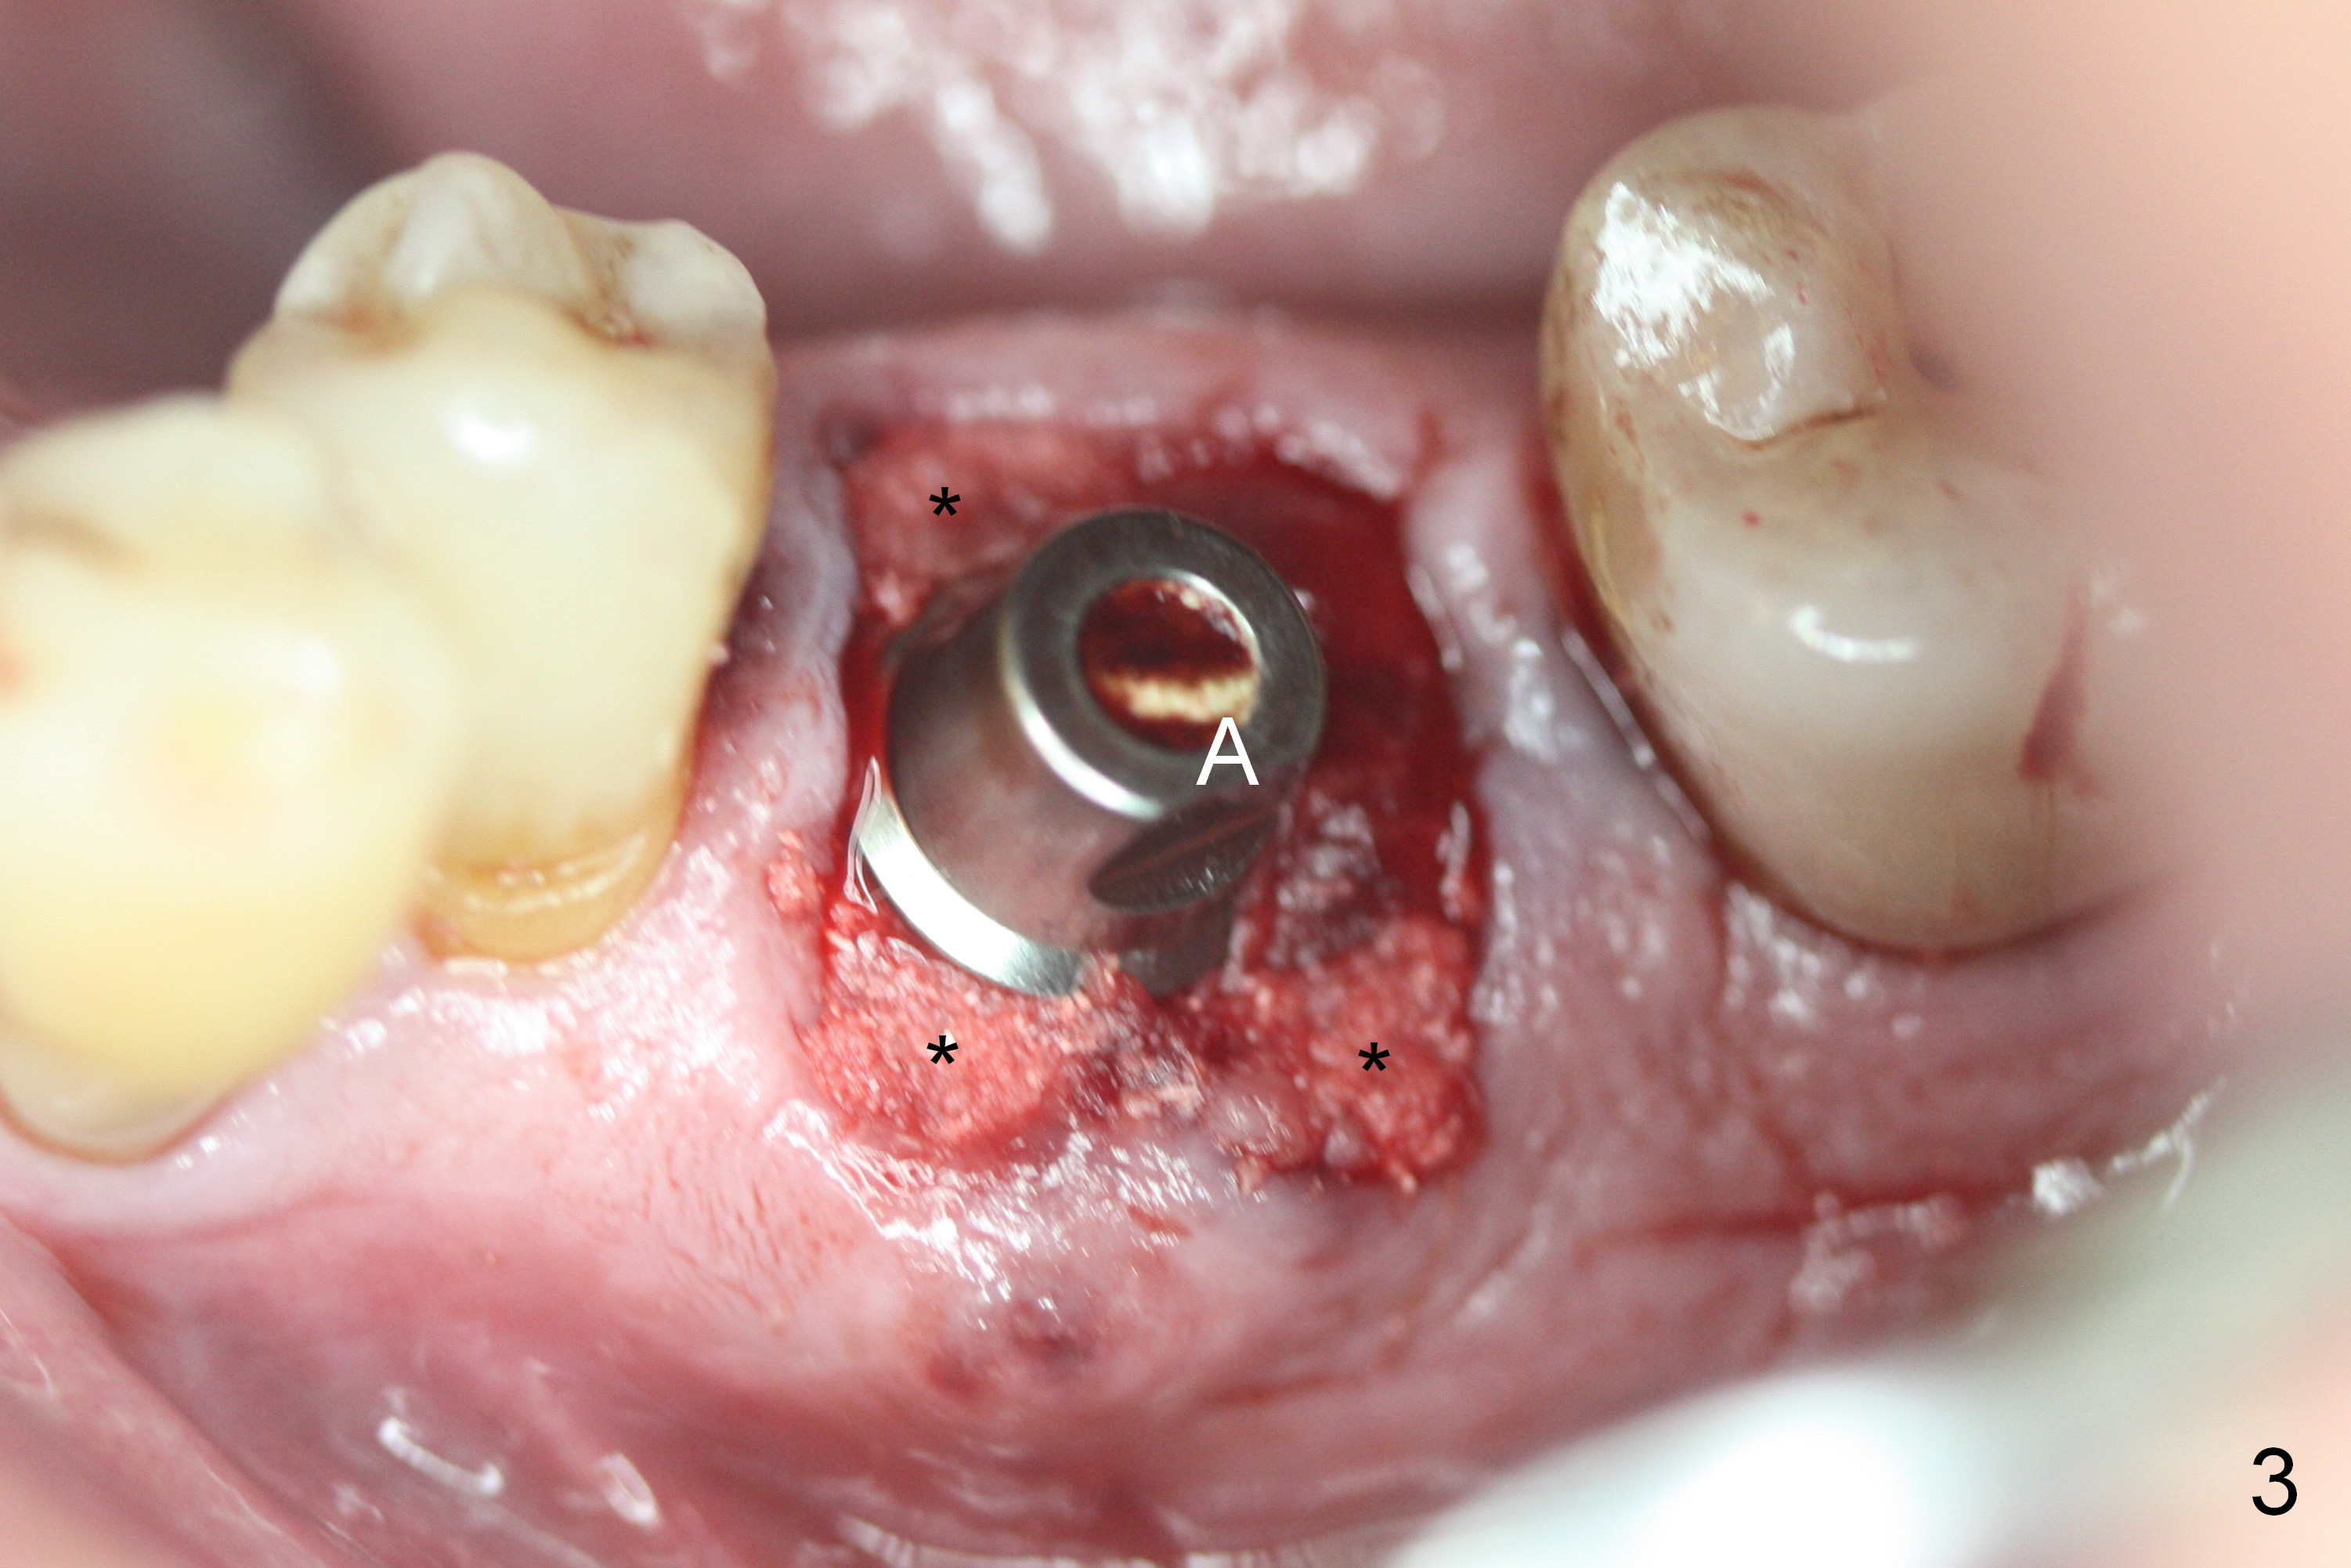

A fistula is found to be associated with the furca when the patient returns for extraction (Fig.1 <). Although the mesial socket is deeper than the distal one, no granulation tissue is curetted from the mesial. Osteotomy is set in the middle of the septum by making a slot first. When the osteotomy is enlarged by 4 mm reamer (Fig.2 R), the latter has been deviated mesial to the septum (*). By manipulating, the coronal end of 6x12 mm implant and 6.5x4(3) mm abutment (Fig.3 A) are placed somewhat in the middle of the socket. An immediate provisional is fabricated to cover the socket and bone graft (Fig.4 P). The exposed bone graft (Fig.4 *) is then covered by perio dressing. Off axial placement of the implant (Fig.5 I) and abutment (A) is striking in the immediately postop PA (Fig.5).